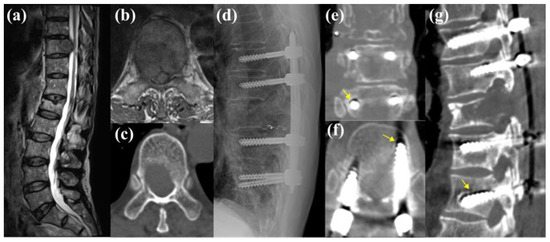

3.5.2. Case 2